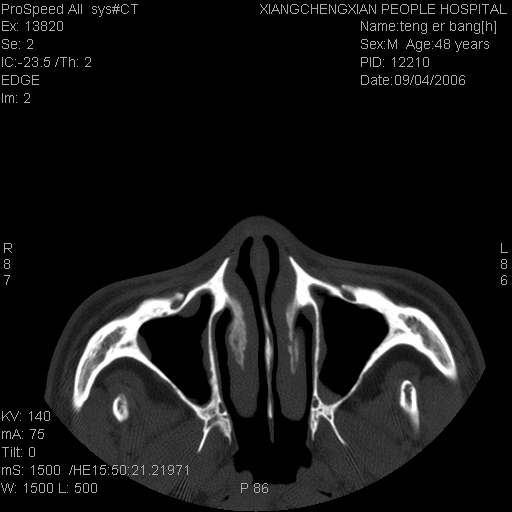

患者,男,以头面部外伤后头疼1小时为主诉入院,患者1小时前被他人打伤头部及左侧面部,眼睑无水肿,左侧面部肿胀压疼,未触及骨擦音。专科检查:耳鼻喉未见异常。

ct:平扫+冠扫:双侧鼻骨对比,冠扫s6#示右侧鼻骨尖部可见线状低密度影,边缘光滑,并见硬化.软组织未见肿胀.

诊断意见:鼻额缝(鼻骨与上颌骨额突缝),但个别同志认为是骨折.因此请同行们会诊.多谢了!

正常鼻颌缝。软组织无肿胀。鼻腔无积液积血。鼻骨光滑规整无中断。均不支持骨折。

正常的,双侧对称.边缘光整,且逢等宽.

正常鼻颌缝。软组织无肿胀。鼻腔无积液积血。鼻骨光滑规整双侧对称。均不支持骨折。